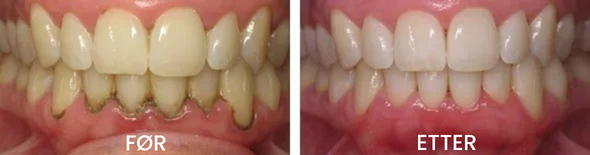

✅ UMIDDELBAR LINDRING – Innen 5–10 minutter vil du kjenne betydelig lettelse fra sensitiviteten. På bare noen dager merker du at tannkjøttet begynner å feste seg igjen. Med jevnlig bruk vil du se tannkjøttlinjen gradvis komme tilbake til en sunnere posisjon.

✅ 100 % MEDISINFRI – Du kan nå regenerere tannkjøtt uten dyre transplantater, smertefulle restitusjonsperioder og høye tannlegeregninger. Støttet av 100 vitenskapelige studier.

✅ FUNGERER FOR ALLE ÅRSAKER – Testet, anbefalt og brukt av hundrevis av tannleger, enten tilbakegangen skyldes for hard børsting, periodontitt, genetikk, hormoner, tannpressing eller feilbitt.